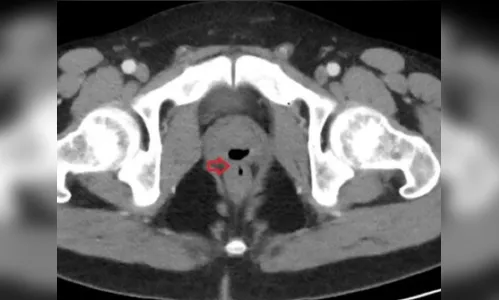

Outros exames identificaram fústula — uma passagem anormal — entre a uretra e o reto, por onde fluidos corriam. O homem foi submetido a uma cirurgia. Os médicos descobriram, também, que, quando esteve em coma, o paciente recebeu um cateter que poderia ter causado as complicações. O caso foi registrado na revista científica Cureus.